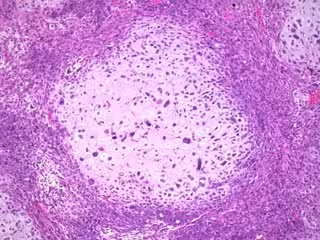

El estudio consistió en identificar los cánceres ginecológicos --vulva, vagina, cuello uterino, cuerpo uterino y ovario-- que algunas de estas mujeres desarrollaron después de su primer cáncer de mama.

De entre todos los tipos de cánceres ginecológicos, sólo se observó un aumento significativo en el riesgo de cáncer de endometrio --el tipo de cáncer de cuerpo uterino más frecuente-- que se vio incrementado más del doble, un 128%, en comparación al riesgo de tener un cuerpo de útero en la población general.